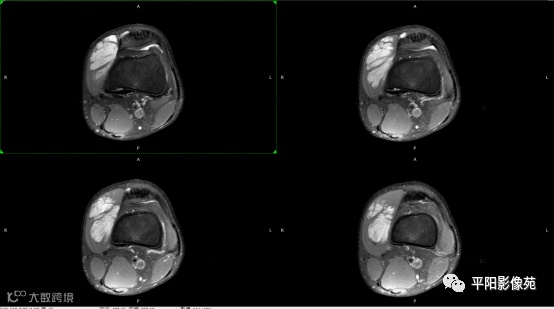

影像表现:

左膝关节股内侧肌内见多房样短T1长T2信号,内可见分隔,增强扫描明显强化,分隔未见明显强化,病灶局部与股骨远端分界不清。